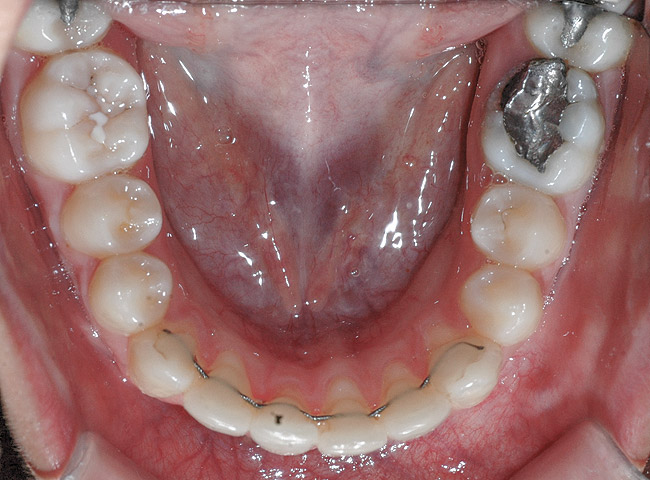

CASE 6 Fig 14. Post-orthodontic Miller Class II recession treated with a combined orthodontic-surgical approach. Clinical view 5 years after first orthodontic treatment showing GR of right lower incisor and a labially prominent root.

Figure 14

Fig 15. Same patient 2 years later showing worsening of GR and inflammation.

Figure 15

Fig 16. Occlusal view of patient shows the difference in angulation between the affected and the adjacent incisors.

Figure 16

Fig 17. Lateral view of same patient showing the root prominence.

Figure 17

Fig 18. CBCT sagittal view shows no bone on the labial aspect and 2.5 mm bone thickness on the lingual aspect.

Figure 18

Fig 19. Frontal view showing the orthodontic appliance used in same patient.

Figure 19

Fig 20. Occlusal view after second orthodontic treatment showing corrected B-L inclination.

Figure 20

Fig 21. Frontal view shows narrowing of the GR.

Figure 21

Fig 22. Frontal view of same patient 4 weeks postsurgical root coverage.

Figure 22

Fig 23. Same patient at 3-year follow-up visit showing a stable esthetic result.

Figure 23